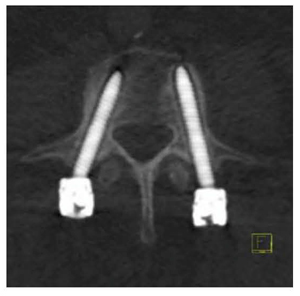

●後方椎体間固定術のフォローアップ

後方椎体間固定術を行った当院の症例では,120kVp相当のweighted-average image(図6a)や,80keVのmonoenergetic image(図6b)では,金属アーチファクトによりスクリューの状態を観察することは難しい。一方,130keVのmonoenergetic image(図6c)では,比較的明瞭にスクリューの溝まで観察することができ,術後早期からスクリューの弛みの状態を確認することができると考えられる。

なお,2011年にEuropean Radiology誌でBambergらが,DEイメージングにて,術後早期にスクリューの弛みの状態がスクリュー表面の透亮像として認められたことを報告している(図7)4)。

図6 metal artifact reduction

図7 loosening of pedicle screws4)